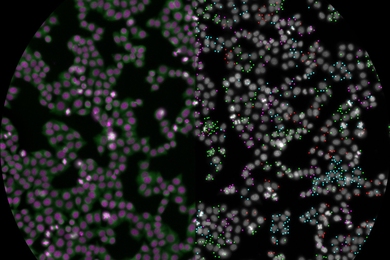

“Spleen-on-a-chip” yields insight into sickle cell disease

With this microfluidic device, researchers modeled how sickled blood cells clog the spleen’s filters, leading to a potentially life-threatening condition.